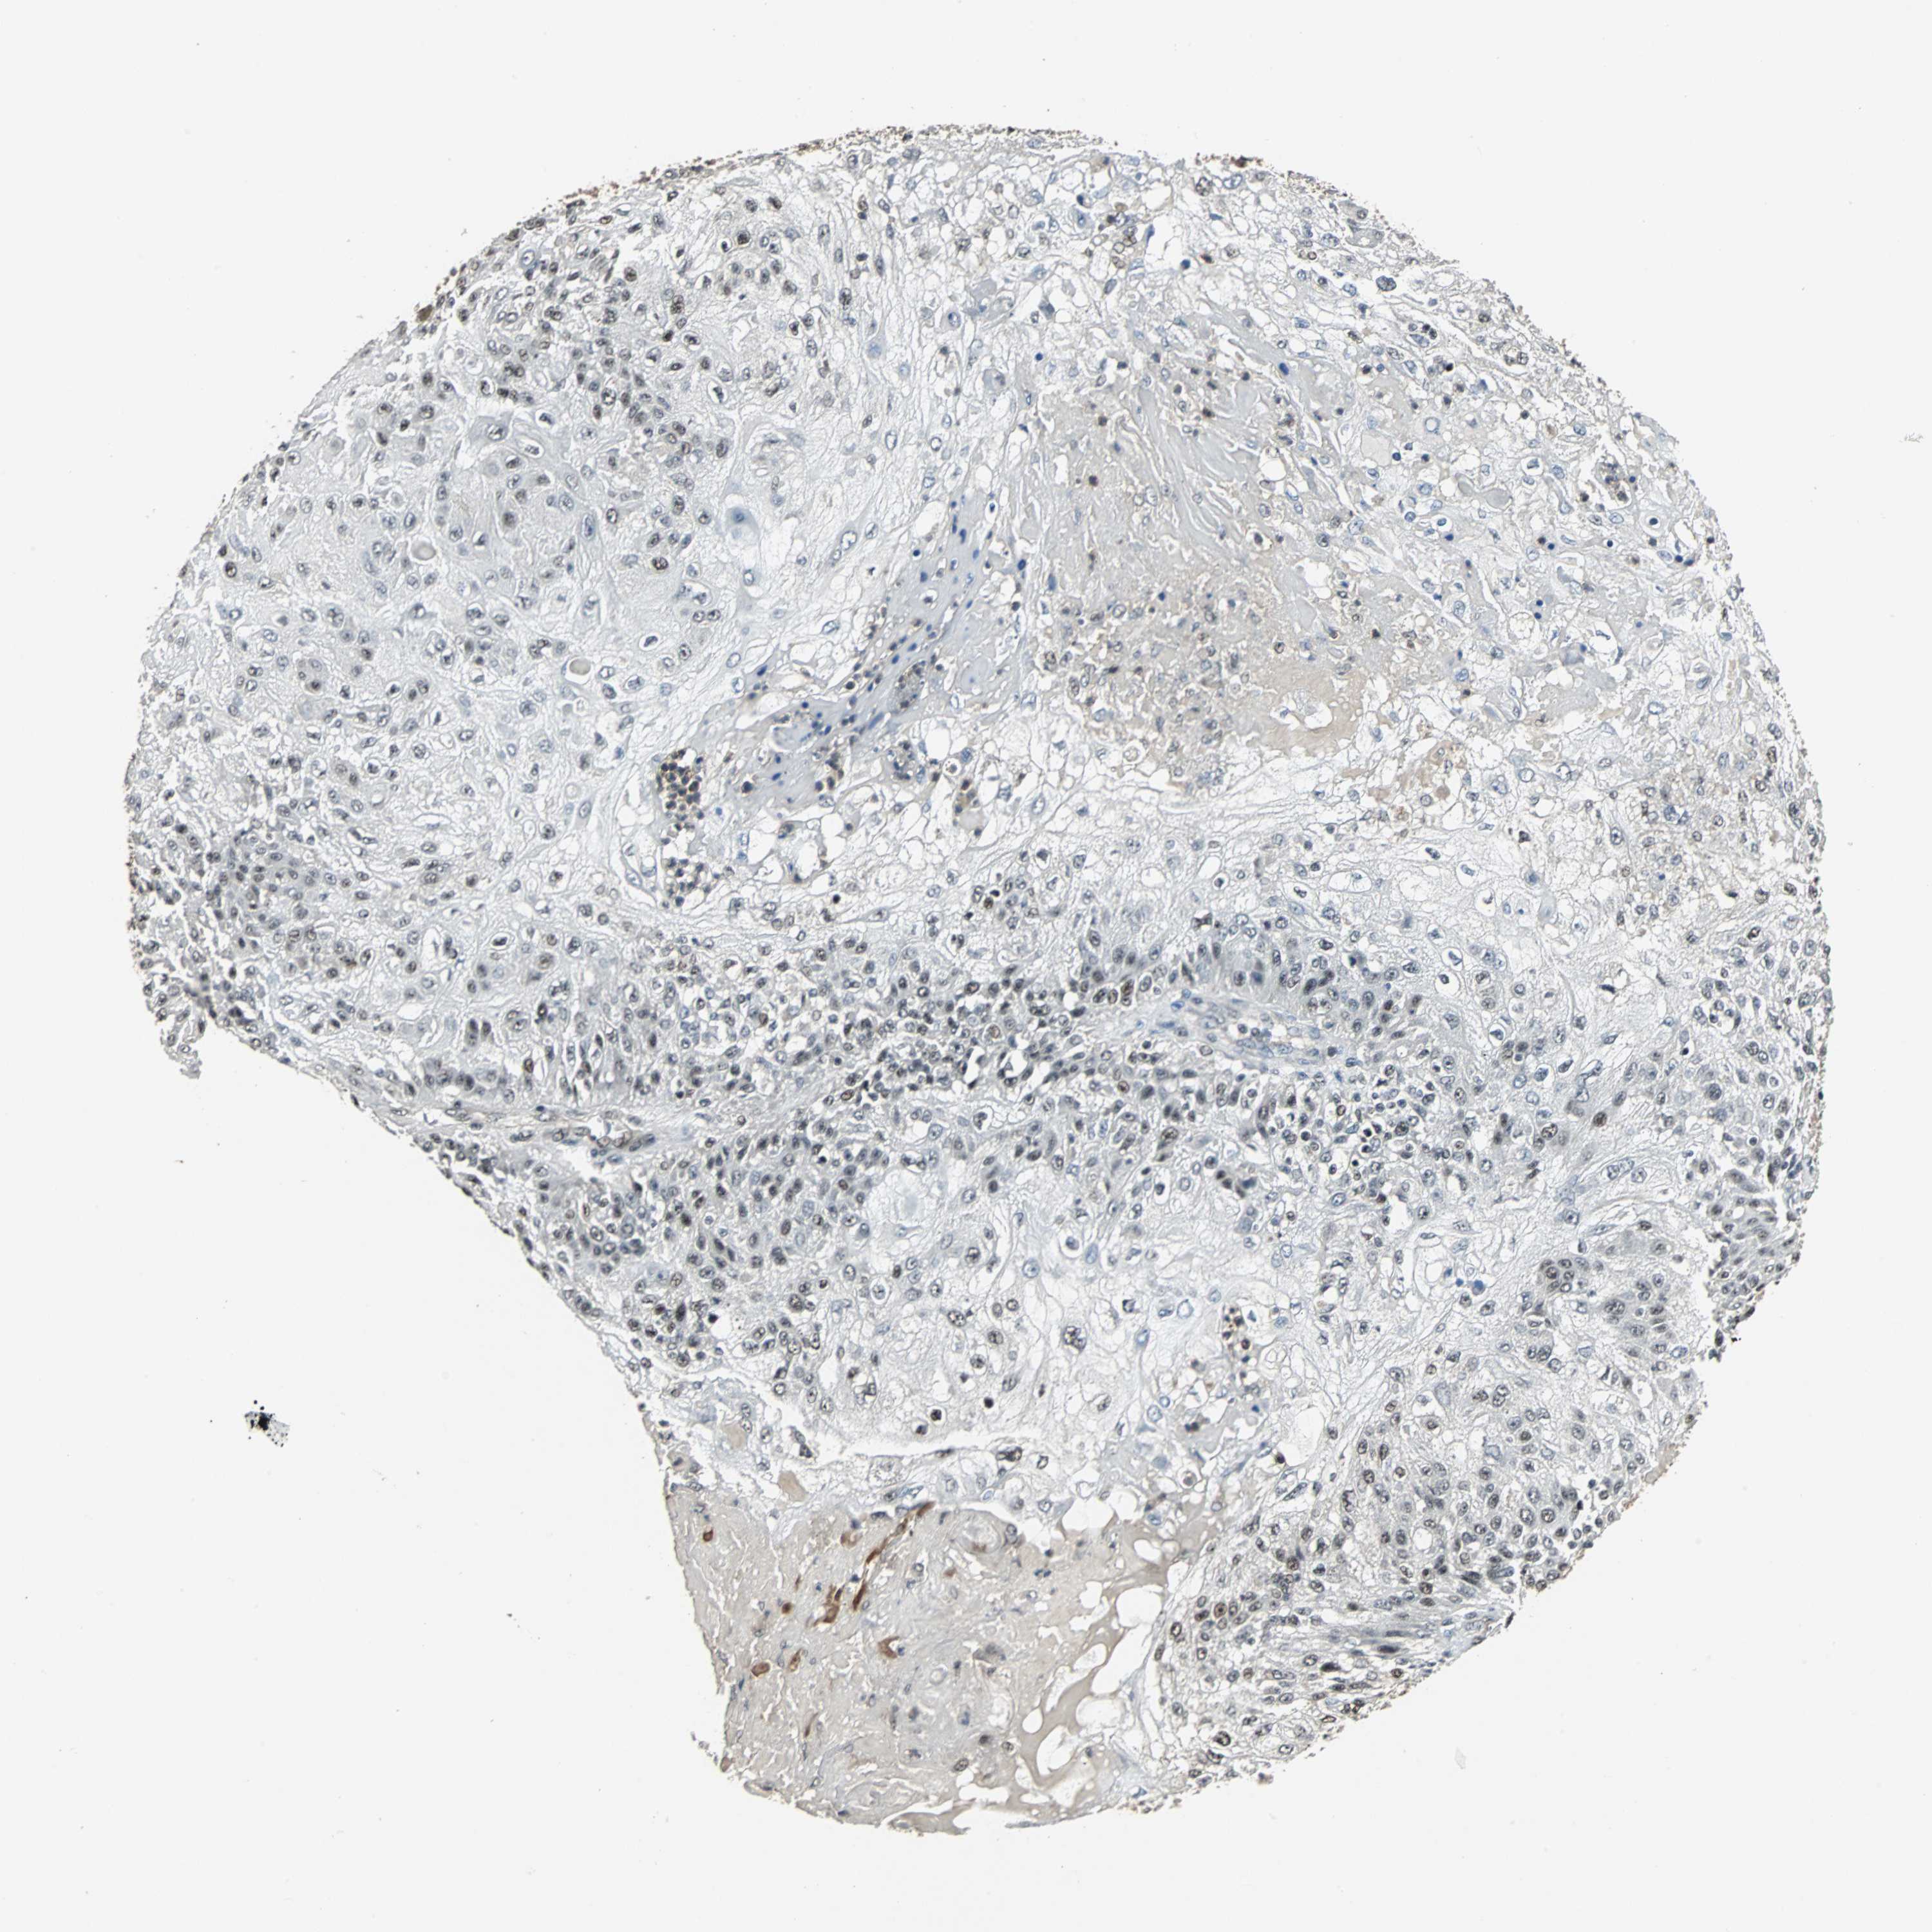

SKIN CANCER - Protein expressioni

A mouse-over function shows sample information and annotation data. Click on an image to view it in a full screen mode. Samples can be filtered based on level of antibody staining by selecting one or several of the following categories: high, medium, low and not detected. The assay and annotation is described here.

Antibody staining in the annotated cell types in the current human tissue is reported as not detected, low, medium, or high, based on conventional immunohistochemistry profiling in selected tissues. This score is based on the combination of the staining intensity and fraction of stained cells.

Each image is clickable and will lead to virtual microscopy that enables deeper exploration of all samples and also displays staining intensity scores, fraction scores and subcellular localization as well as patient and tissue information for each sample.

Antibody HPA006232

Staining

Not detected

Negative

<25%

None

Basal cell carcinoma